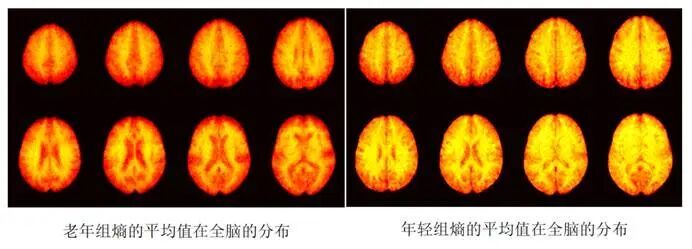

在脑功能复杂度分析方面,研究团队提出多变量样本熵分析算法,在利用原始fMRI信号进行复杂度分析的同时,结合T2信号协同计算神经活动复杂度。该算法在年轻与老年人群中进行了验证实验,结果显示,在部分脑区中年轻组与年老组之间存在显著差异,有效提升了fMRI复杂度分析的可靠性。

多变量样本熵算法在年老组和年轻受试组的fMRI时间复杂度分析结果